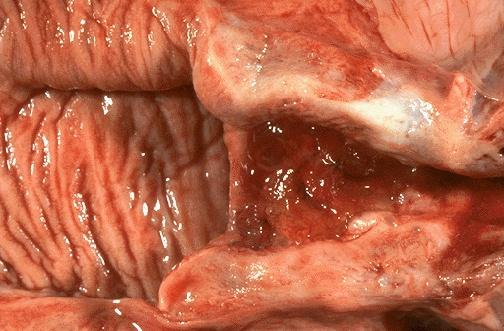

阴道壁